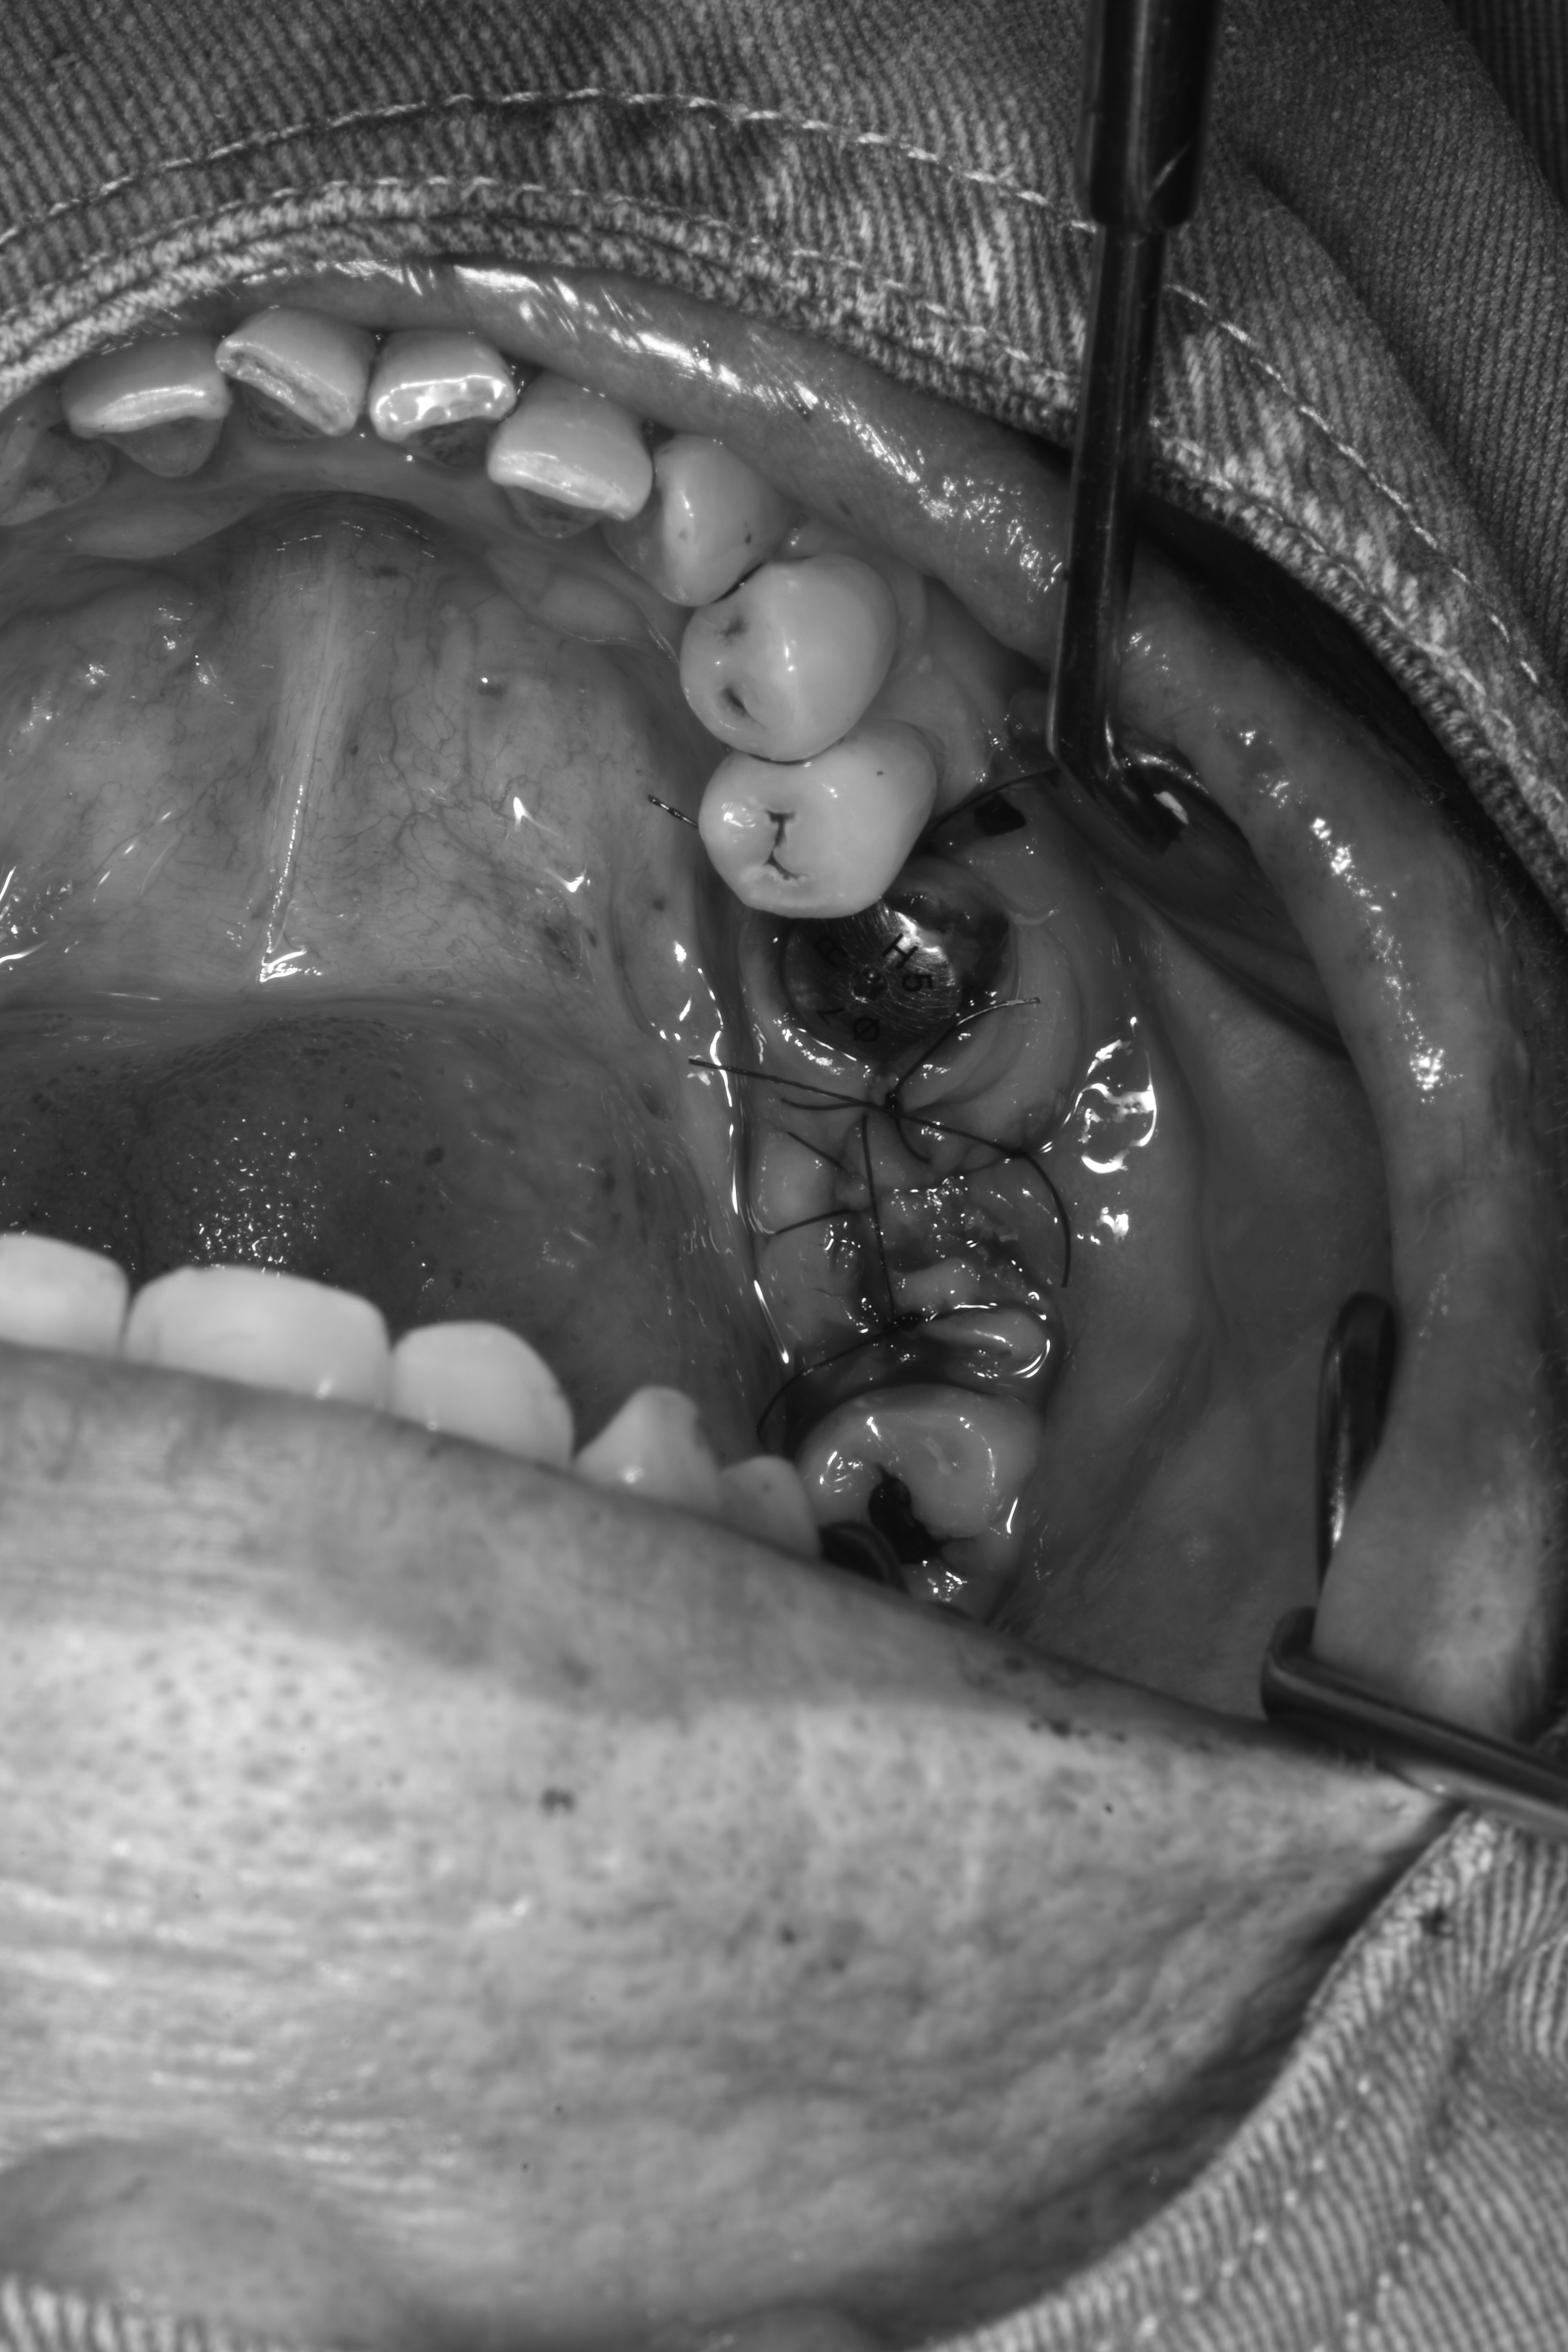

立即式植牙(即拔即種)